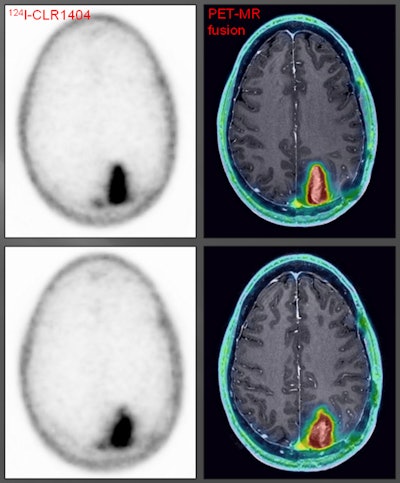

CLR1404-PET successfully imaged tumors with high tumor-to-background uptake and uncovered larger tumor volumes than contrast-enhanced MRI.

"We saw areas of concordant and discordant PET uptake and MRI enhancement," Hall said. "This is what we are really excited about, those discordant areas. Those are the areas where we have the ability to add perhaps more accurate complementary information to what MRI shows."

Patient with a grade III glioma is imaged with T2-weighted MRI (above left). Follow-up gadolinium-enhanced MRI (above right) suggested cancer recurrence. CLR1404-PET detected cancer (below left) and fused PET/MRI (below right) delineated the tumor. All images courtesy of Dr. Lance Hall and UW Health.